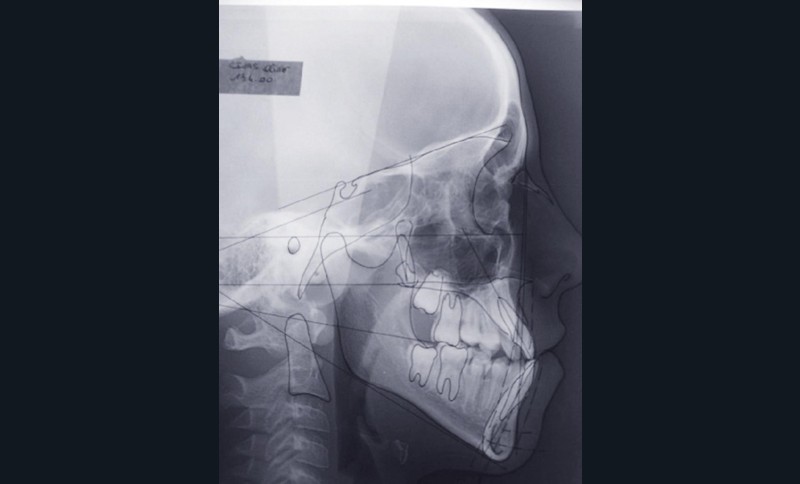

Olivier se présente à l’âge de 12 ans avec une classe III squelettique à prédominance mandibulaire, accompagnée d’une hyperdivergence et d’une endomaxillie responsable des inclusions des canines supérieures à forte obliquité. Une phase d’expansion est réalisée afin de permettre une augmentation du périmètre de l’arcade et la verticalisation des germes des canines. L’expansion permet en effet une normalisation transversale mais ne permet pas de réaliser la mise en place des canines. Les extractions des prémolaires sont alors effectuées et une préparation primaire de l’arcade supérieure par multi-attaches avec désinclusions et tractions des canines est réalisée.

Une pause thérapeutique est ensuite entamée jusqu’à la fin de croissance soit 18 ans. Une poursuite du traitement par préparation secondaire à la chirurgie orthognathique bimaxillaire est programmée.

Les mouvements de décompensations sagittales et transversales sont réalisés à l’aide des tractions inter-arcades. La réévaluation céphalométrique et l’analyse des moulages confirment l’indication d’une chirurgie maxillaire de propulsion et d’une chirurgie mandibulaire par clivage bilatéral des branches montantes pour un recul mandibulaire modéré accompagné d’une génioplastie bidimensionnelle élargie qui rappelle la technique de Chin Wing.